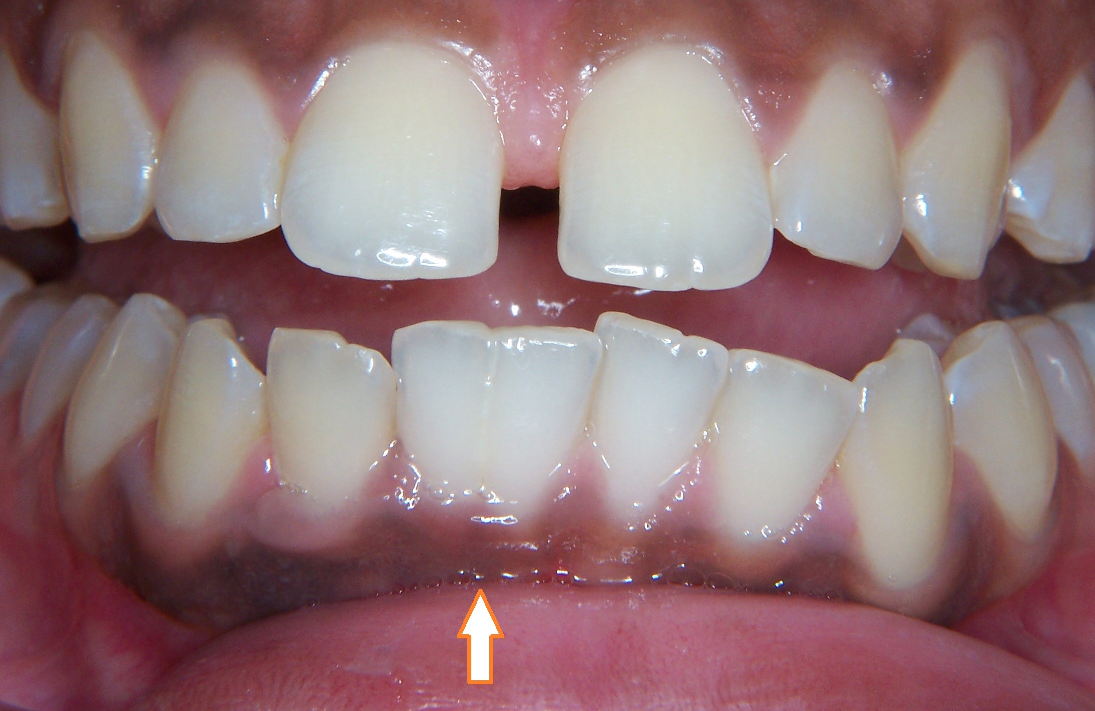

patient walks in count was one less than normal. what do they have?

FUSION

always anterior

2 buds merge into 1 tooth